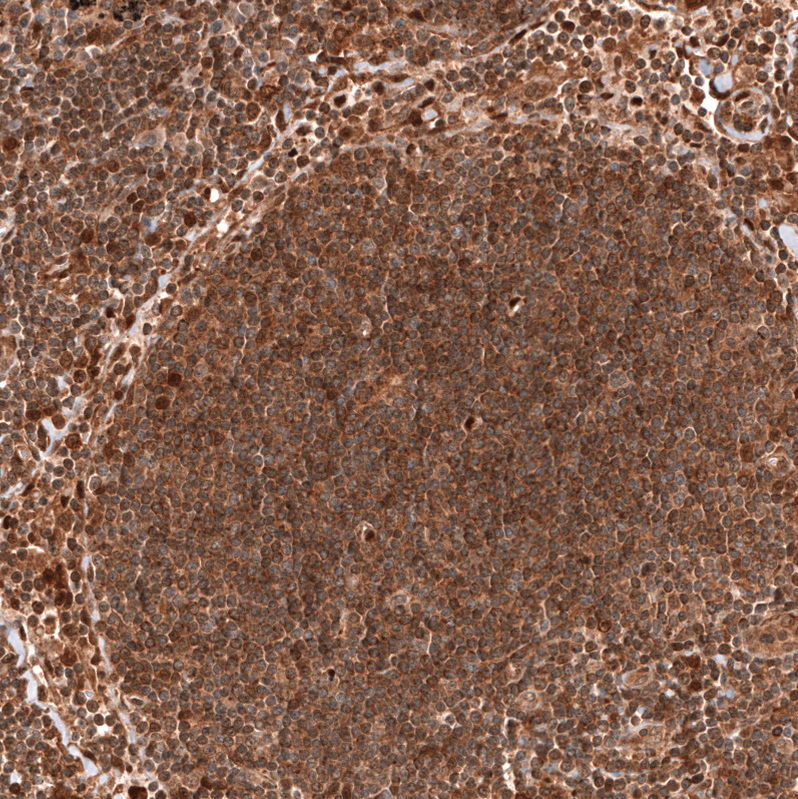

Immunohistochemistry analysis in human lymph node and skeletal muscle tissues using AMAb91735 antibody. Corresponding PTEN RNA-seq data are presented for the same tissues.